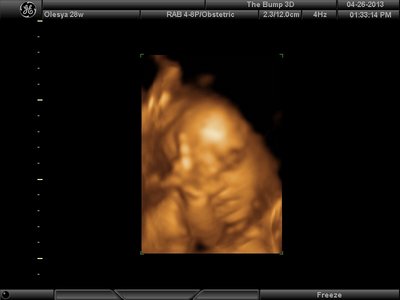

А я вчера на 3Д УЗИ ходила. Моя звезда закрывалась в еми 4мя конечностями. Просто пополам сложилась и спала себе сладко. УЗИстка провела со мной час, кое-как расшевелили маленькую, но ручка была постоянно на мордашке и засыпала она почти сразу снова. Я и на мяче прыгала и живот трясла. В конце более-менее фото вышли, но качество меня не порадовало. Возможно фри оф чардж еще раз переделают. Со средней фотки были отличного качества, а эти сплошное разочарование. Вот тут что-то более-менее еще. Главное пальчик оттопырила так смешно, мол минуточку. Вообще немного жутковатые фотки..хаха

image.jpg [ 47.86 КБ | Просмотров: 1240 ]

Еще одна, качество ужасное..

image.jpg [ 60.32 КБ | Просмотров: 1237 ]